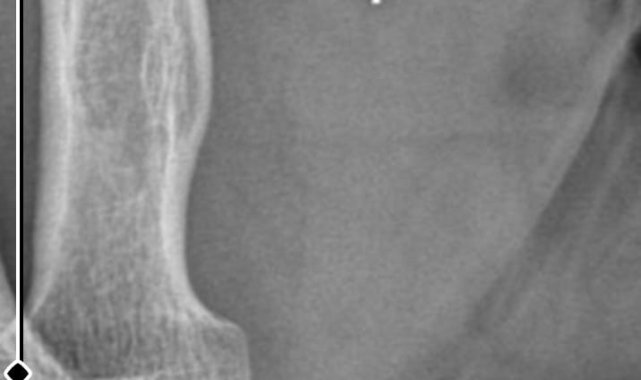

Kocaeli'de Kurban Bayramı'nda yaşadığı bıçak kesiğinin ardından başvurduğu iki özel hastanedeki yanlış tedavi iddiaları sebebiyle parmağı ampute edilen ve çalışma kabiliyetini kaybederek işinden olan Nurettin Güleryüz, "tıbbi ihmal" iddiasıyla tedaviyi yürüten doktorlar hakkında suç duyurusunda bulundu.Edinilen bilgiye göre, 7 Haziran 2025'te Kurban Bayramı dolayısıyla bıçak temizlerken sağ el başparmağını kesen Nurettin Güleryüz (34), bir özel hastanenin acil servisine başvurdu. İddiaya göre, hastanede detaylı tetkik yapılmadan pansuman uygulanan Güleryüz'e ilaç reçete edilerek taburcu edildi. Şikayetlerinin devam etmesi ve kanamanın durmaması üzerine ertesi gün aynı hastaneye tekrar giden Güleryüz'e bu kez dikiş atıldı.Parmağını hareket ettirememesi üzerine 19 Haziran'da Gebze'deki başka bir özel hastaneye başvuran Güleryüz, tendon yaralanması şüphesiyle tedaviye alındı. Farklı tarihlerde yapılan EMG ve MR tetkiklerinde sinir hasarı ile tendon kopması tespit edilen hasta, 2 Eylül'de ameliyat edildi. Süreç içerisinde parmağın çürüdüğü ve kurtarılamayacağının belirtilmesi üzerine Güleryüz, başvurduğu başka bir hastanede ampute operasyonu geçirdi.Öte yandan, ameliyatların ardından ağrıları devam eden Güleryüz'ün kolunda metal parça bulunduğu ve bu parçanın parmak bölgesinden dirseğe doğru ilerlediği öne sürüldü. Ayrıca, fabrikada temizlik personeli olarak çalışan Nurettin Güleryüz'ün hastane sürecinde işten çıkarıldığı da öğrenildi."Yüzde 46 olan engellilik oranı yüzde 75'e yükseldi"Güleryüz'ün avukatı Barış Kurt, Gebze Cumhuriyet Başsavcılığına sunduğu şikayet dilekçesinde, özel hastanede görevli hekimlerin tıp kurallarına aykırı hareket ederek ihmalde bulunduklarını ileri sürdü. Olayın basit tıbbi komplikasyon olmadığını savunan Kurt, "Başparmakta oluşan kesilerde tendon ve sinir hasarı ihtimali basit muayene ile dahi anlaşılabilecek durumdur. Buna rağmen şüpheli hekimler gerekli özeni göstermemiştir. Doğru teşhis zamanında konulmuş olsaydı, gerekli cerrahi müdahale gecikmeden yapılacak ve müvekkil kalıcı sakatlık yaşamayacaktı. Müvekkilin yaralanma öncesinde yüzde 46 olan engellilik oranı, yaşanan süreç sonrası yüzde 75'e yükselmiştir. Bu durum müvekkilin yaşamını ve çalışma gücünü ciddi şekilde etkiledi. Sorumlular hakkında taksirle yaralama, görevi kötüye kullanma ve ihmali davranışla yaralama suçlarından soruşturma yürütülmesini talep ediyoruz" dedi."Parmağı pansumanın ardından yapıştırıp gönderdiler" iddiasıYaşadıklarını anlatan Nurettin Güleryüz ise "Kurban Bayramı'nın ikinci günü bıçağı temizlerken yanlışlıkla parmağımı kestim. Özel hastaneye gittim ve doktorla görüştüm. Doktor bize parmağın yapıştırılması gerektiğini söyledi. Parmağı pansumanın ardından yapıştırıp gönderdiler ve ilaç yazdılar. İlaç yazdıkları halde herhangi bir film, röntgen çekilmedi. Parmağımın kanaması devam edince ikinci akşam yine hastaneye gittik. Parmağıma dikiş attılar ve yine röntgen, film çekmeden herhangi işlem yapmadan gönderdiler. Bu süreçte pansumanlarımızı yaptırdık. Bundan sonra bize 10 gün süresince pansuman yapmamız gerektiğini söylediler. Bayram tatili olduğu için hiçbir yere gidemedik" diye konuştu."Çürümüş parmağı içeriye nasıl katlayabilirsiniz"Güleryüz, bayramın ardından başka bir özel hastaneye başvurduğunu anlatarak, "Buradaki hastanede acil ameliyata alınmam gerektiği söylendi. Burada da MR veya herhangi tetkik yapılmadan ameliyata alındım. Ondan sonra 2 kez daha ameliyat geçirdim. Bu süreçte doktorlar parmağımın kurtarılamayacağını söyledi. Parmağımın tendon damarı ve sinir damarı tutmadı. Parmağım çürümeye başladı. Bize yaptıkları teklif şu oldu; 'Parmağı bükeriz, katlayıp geriye bırakırız' dediler. Biz de kabul etmedik. 'Çürümüş parmağı içeriye nasıl katlayabilirsiniz?' dedik. Onlar da yapacak başka çarelerinin olmadığını söylediler. Biz de başka hastanelerden randevu aldık ve başka hastanelere gittik. Parmağın ampute edilmesi gerektiği söylendi. Parmağım ampute edildi. Büyük ihtimalle ikinci gittiğim hastane sebebiyle parmağımı kaybettim çünkü ameliyatlardan sonra herhangi röntgen ya da MR çekimi yapılmadı. Bunu doktora söylediğimiz halde doktor bizi dinlemedi. Bize 'iyiye gidiyor' dedi" ifadelerini kullandı."Pazartesi günü bunun için de operasyon geçireceğim"İkinci hastanedeki ameliyatların ardından kolunda ağrılar hissettiğini söyleyen Güleryüz, sözlerini şöyle noktaladı:"Doktorlara bileğime doğru ağrılarım olduğunu sürekli ifade etmeme rağmen beni dinlemediler. Sonradan kolumda metal kaldığını öğrendik. Bunun ihmal olduğunu düşünüyoruz. Çünkü kola metal nasıl girebilir? Ben 9 aydır çalışamıyorum. Kalp rahatsızlığım sebebiyle yüzde 46 engelliyken şu anda yüzde 75 engelli durumuna düştüm. Erken emeklilik dilekçesi verdim ancak henüz sonuç gelmedi. Bu konuda çok mağdurum. Yetkililerin bunu duymasını istiyorum. Savcılığa suç duyurusunda bulunduk. Yaklaşık 9 aydır henüz soruşturma izni gelmedi. Süreci bekliyoruz, henüz dava açılmış değil. Kolumda bırakılan metal ilerliyor. Pazartesi günü bunun için de operasyon geçireceğim. Çıkarılıp çıkarılamayacağı net değil. Elimde titremelerim var, çalışamıyorum ve işveren tarafından işten çıkarıldım. Yetkililerden destek ve konunun incelenmesini talep ediyorum."